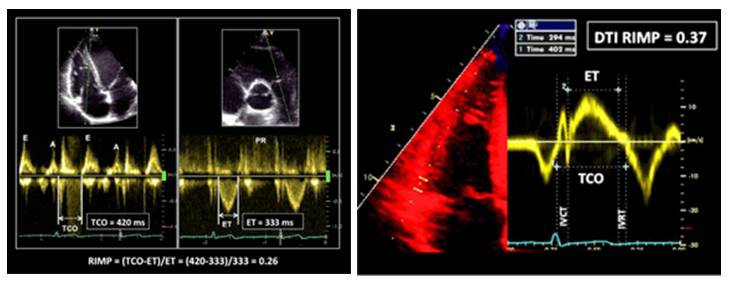

RV整体功能: Tei 指数 (RIMP)

2015 ASE成人心腔定量测量指南